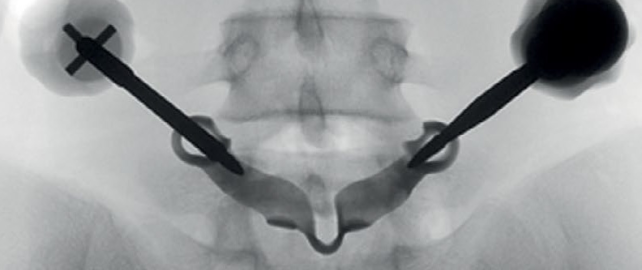

Оперативное лечение двустороннего спондилолиза L5 позвонка у профессиональной гимнастки с использованием индивидуальной конструкции